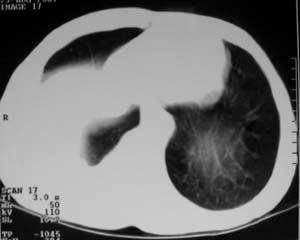

男,54岁,无任何不是感.体检发现右肺部阴影.现行ct进一步确诊.

右侧胸廓塌陷,肋间隙变窄,肋骨增生变粗,脏壁层胸膜肥厚、钙化。符合陈旧性结核性脓胸改变

右侧包裹性积液伴胸膜钙化.

右侧包裹性积液并胸膜钙化,性质还是结合穿刺细胞学检查的好,结核性、化脓性均会有钙化。

右侧胸膜肥厚、粘连、钙化。

周围都钙化了应该不是积液了吧,这样都没有不适感,病史不详